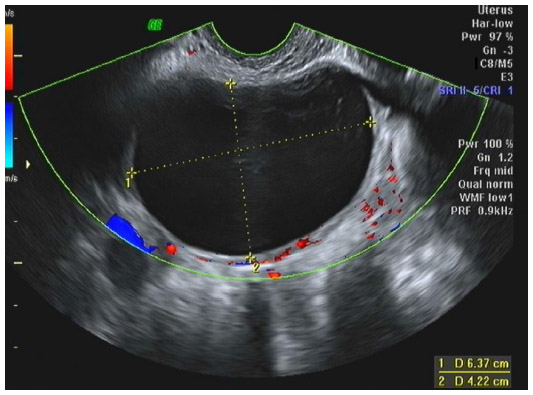

Introduction Adnexal masses can be benign or malignant, ranging from simple functional cysts to ovarian carcinomas. The clinical challenge is